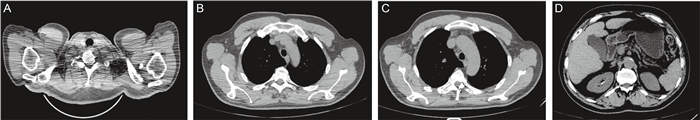

入院时查体生命体征平稳,神清,皮肤苍白,巩膜无明显黄染,无皮疹及出血点,无肝掌及蜘蛛痣;双肺呼吸音粗,未闻及干湿啰音;心脏听诊无异常;腹软,全腹无明显压痛、无反跳痛,肝脾肋下未触及,移动性浊音阴性,肠鸣音正常,双下肢无水肿。入院查白细胞指标值正常,血红蛋白84 g/L,C反应蛋白(C-reactive protein,CRP)15.9 mg/L,降钙素原正常,肝功能正常,肿瘤标志物全套均正常,乳酸脱氢酶正常,血清β2微球蛋白4.6 mg/L。人类免疫缺陷病毒(human immunodeficiency virus, HIV)抗体阴性。胸部及全腹部计算机断层扫描(computed tomography,CT)提示肺下叶背侧坠积性炎性改变,双侧胸膜增厚粘连;胃壁增厚;纵隔、双侧腋窝、腹膜后及肠系膜走行区淋巴结增多、肿大,较大者2.0 cm,不排除转移性病变;双侧肾上腺明显增粗,不排除转移性病变;腹盆腔积液(见图 1)。

A: Increased and enlarged lymph nodes in neck in CT scanning. B: Increased and enlarged lymph nodes in axilla in CT scanning. C: Increased and enlarged lymph nodes in mediastinum in CT scanning. D: Bilateral adrenal gland thickening and increased and enlarged lymph nodes in mediastinum in CT scanning. 图 1 胸部及全腹部CT检查结果(2021年4月) Fig. 1 CT examination results of chest and abdominal (April 2021) |